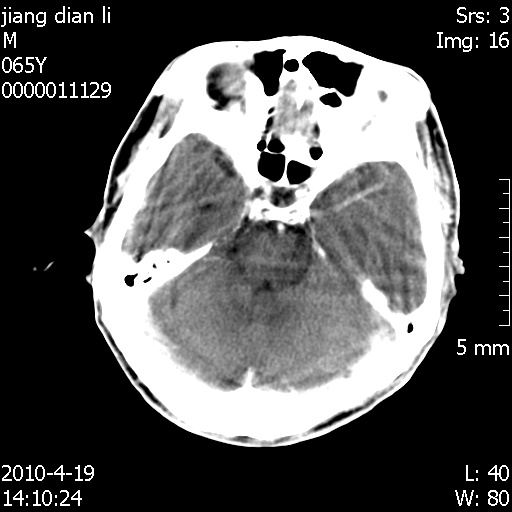

老年男性,突发左下肢无力1天,其余有价值的检查都没有。平扫ct值大约60hu,增强后ct值没什么改变,请大家讨论一下这个病例是什么?说明诊断理由。

左小脑、右大脑顶叶多发圆形高密度病灶,其周环状低密度影。考虑多发脑出血。隔期观察。

至于是出血还是微小钙化所致的高密度无法考证,三个都出血也不是一点都不可能,同一种组织学类型的肿瘤受到同一个外来的因素影响后会表现出相同的病理变化。说实在的,我本身支持转移瘤的,就是想不通为什么不强化?我认为单纯脑出血的边缘不会那么光滑,并且那也不是出血的常见部位,多发也不常见。